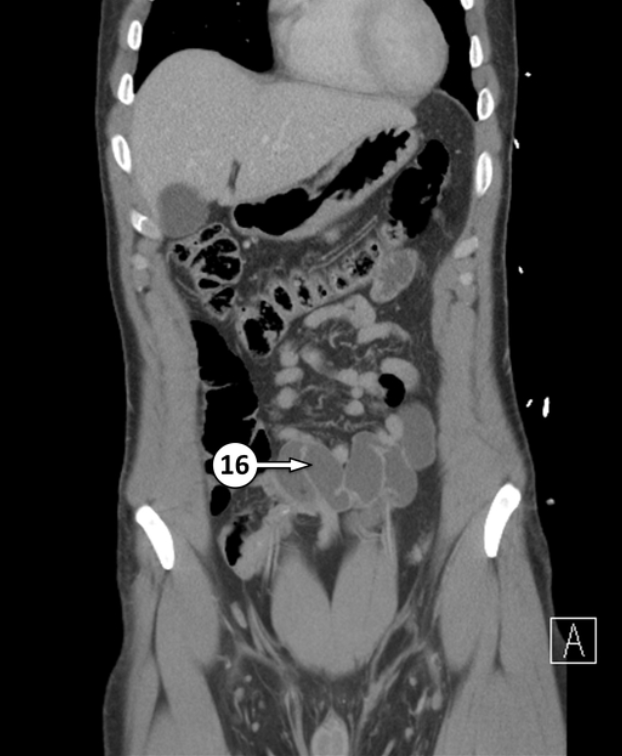

24 is a part of the pancreas. Please label the specific part and the epithelium associated

Neck of pancreas + simple columnar epithelium